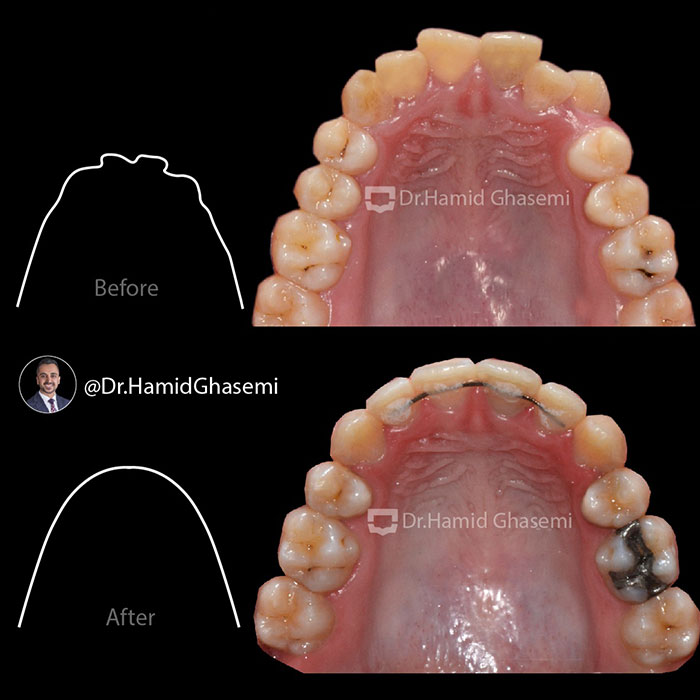

درمان ارتودنسی بدون جراحی در کیس bimaxillary dentoalveolar protrusion (جلوزدگی فک بالا و پایین) با کشیدن دندانهای پرمولر دوم در مدت ۲۰ ماه انجام شد. بهبود بافت نرم صورت و حالت لبها در نمای نیمرخ فتوگرافی و رادیوگرافی لترال کاملا مشهود است.

️Non surgical orthodontic treatment of case with bimaxillary dentoalveolar protrusion done by extraction of 2nd bicuspids within 20 months. Improvement of soft tissue profile and lips posture are obvious in profile photography and lateral ceph xray.